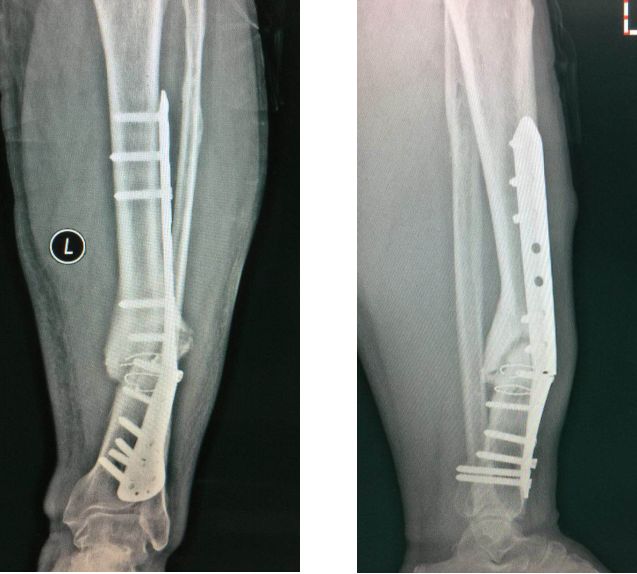

更换长钢板后愈合

补救:取下一枚钉子骨折愈合了,关键是取钉子后减少了应力集中,延长了钢板的寿命,骨折愈合了。如果骨不愈合钢板迟早断裂(钢板当初放在内侧会好,蝶形骨块不会坏死,腓骨固定后外侧稳定,内外柱均衡愈合机会增加,当然最好还是髓内钉)。

取下3枚钉子骨折愈合了,与上一例同一位医生所做。张力带钢板,去除3螺钉后,钢板的应力分散,弹性增加,骨折端承受有效的应力刺激,最后骨折愈合。去除螺钉的时候如果加骨皮质剥离重新激发骨愈合会更好。(最好选髓内钉)